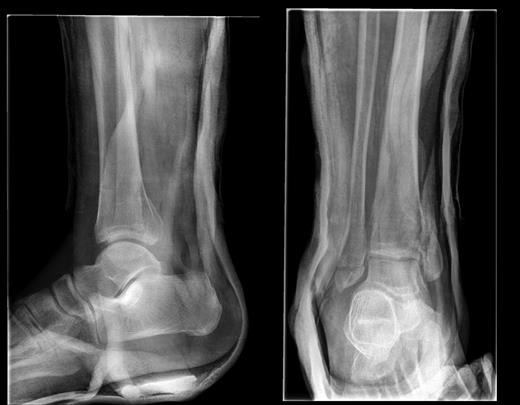

A 51-year-old Afro-Caribbean man sustained a traumatic, closed, tri-malleolar fracture dislocation of his right ankle after falling down 10 steps under the influence of alcohol. He was otherwise fit and well; he is a smoker of 3 per day with occasional binge drinking habits. He was neurovascularly intact; his fracture was reduced in A&E with adequate analgesia before radiographs were taken. He had a lateral malleolar fracture with a vertical shear of the medial malleolus and comminution at the joint line. The fracture may be classified as a Weber A, or Lauge Hansen type 2 (Fig. 1).

AP and lateral radiographs of the fracture post-reduction and immobilization.